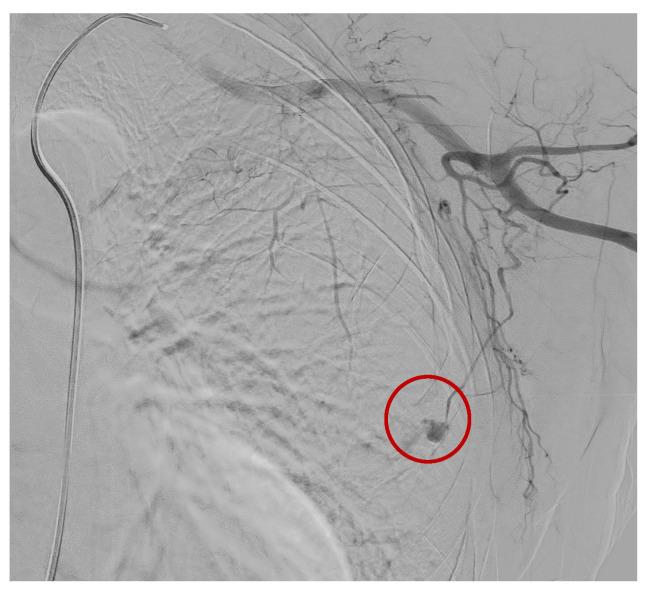

In this article, we aimed to describe a 60 years-old woman who, following VABB, experienced a massive hematoma without external bleeding and was successfully treated with embolization. The woman was called back for a cluster of suspicious microcalcifications identified in the left breast's upper-outer quadrant; however, following histopathological analysis, the few samples collected were negative. She had a silent past medical history, 100% performance status, and no active pharmacotherapy. Approximately 15-30 min after VABB, the patient complained of weakness, pain, and lipothymia. A physical examination revealed a massive hematoma without external bleeding. Clinical data reported PaO 65/40 mmHg and blood chemistry Hb < 10 g/dL. The emergency team was alerted to stabilize the patient, and after that, the breast hemorrhage was controlled by endovascular embolization. Despite this being a rare occurrence, it is important to draw up and follow an appropriate protocol to ensure proper patient management and early treatment.

本文旨在描述一位 60 岁女性,在接受 VABB 后出现无外部出血的大量血肿,并通过栓塞成功治疗。该女性因左乳房上外象限发现一簇可疑微钙化而被召回;然而,组织病理学分析后,仅采集到少量阴性样本。她既往病史无明显异常,表现状态为 100%,且无正在进行的药物治疗。在 VABB 后约 15-30 分钟,患者出现虚弱、疼痛和晕厥。体格检查发现无外部出血的大量血肿。临床数据报告 PaO 65/40mmHg,血化学 Hb < 10g/dL。紧急医疗队被召集以稳定患者,随后通过血管内栓塞控制了乳房出血。尽管这种情况很少见,但制定并遵循适当的方案对于确保患者得到妥善管理和早期治疗至关重要。